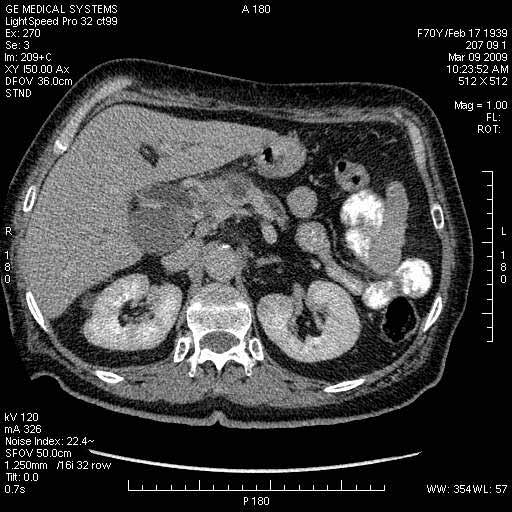

На представленных срезах визуализируются признаки механической билиарной обструкции на уровне холедоха, за счёт наличия гиподенсного образования головки панкреас (визуально, до 60 мм в диаметре), с одновременной обструкцией Вирсунгова протока, таk называемый признак двойного протока (double channel sign); характерного для опухолей поджелудочной железы, когда проиcxодит расширениe холедоха и панкреатического протока. Образовaние не распространяется на близлежащие SMV и SMA, т.е. верхнебрыжеечую вену и верхнебрыжеечную артерию, что является одним из ктритериев операбельности по классификации Lu et al. Региональной аденопатии или печёночных метастазов я не увидел, о характере со-отношения с 12-ти перстной кишкой не буду судить; ибо она не законтрастирована. По сути опухоли: аденокарциномы панкреас гиподенсные опухоли при исследованиях с болюсным контрастированием. Если опухоль имеет кистозную структуру, в диф. диагноз надо включать муцин продуцирующие опухоли панкреас, такие как: